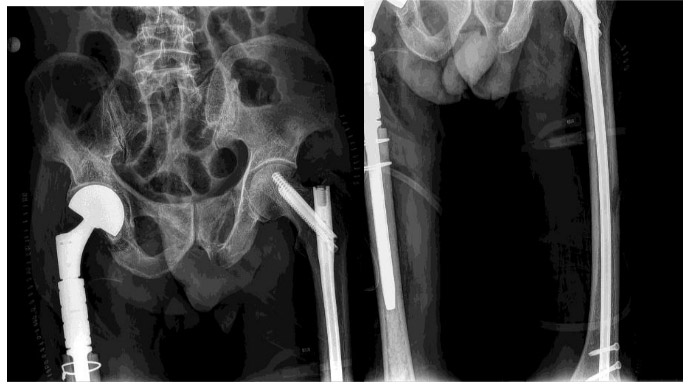

Post-surgery: The X-ray shows a tumor prosthesis placed in the upper part of the right thigh and a nail inserted into the left femur.